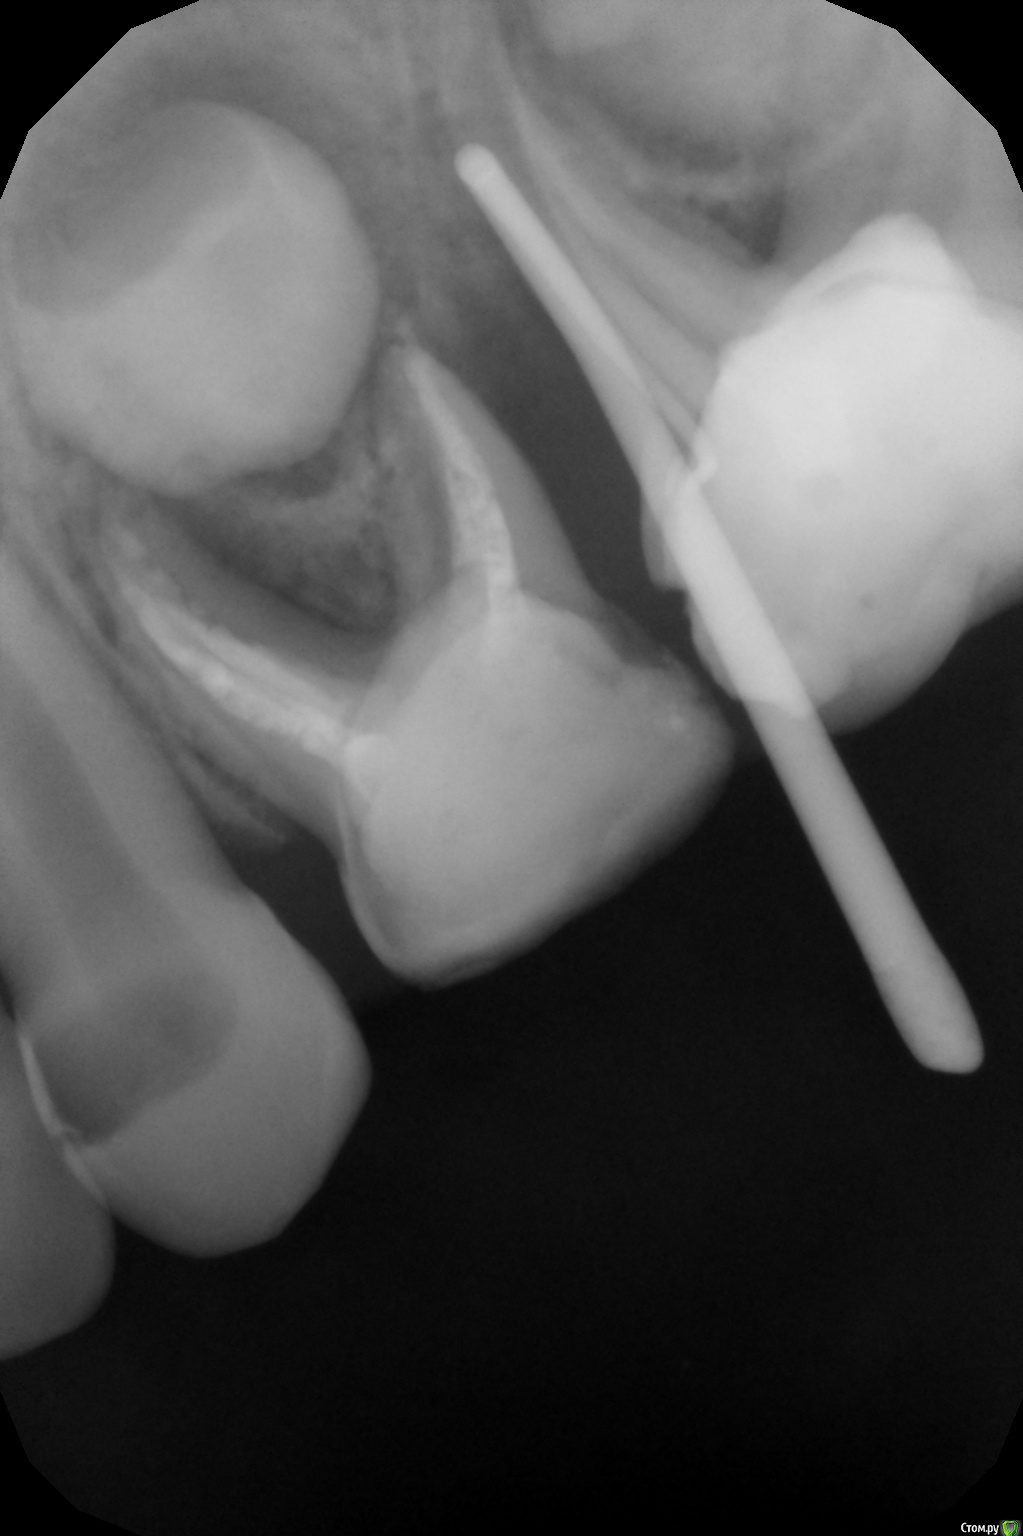

crown Опубликовано 3 июня, 2016 Поделиться Опубликовано 3 июня, 2016 5,5 лет между 85 и 84 свищ. Вввел штифт в свищевой ход. Ссылка на комментарий

crown Опубликовано 3 июня, 2016 Автор Поделиться Опубликовано 3 июня, 2016 (изменено) http://forum.stom.ru/topic/28329-periodontity-lechit-nelzia-udaliat/page-2?do=findComment&comment=498541не?Похоже оно. Я как то читал ваш случай, просто забыл. Получается маргинальный периодонтит. Вот как лечить такое? Как то можно обойтись без экстракции? Изменено 3 июня, 2016 пользователем crown Ссылка на комментарий

Kota Опубликовано 4 июня, 2016 Поделиться Опубликовано 4 июня, 2016 у меня недавно был похожий случай. моя пациентка, между 84 и 85 зубами, зубы ранее депульпированы. меня не было на работе и коллега сделала снимок и предложила удалить 84 зуб. но там девочке уже 7,3. я восстановила контактный пункт с матрицами и клином. ттт все нормально, воспаление ушло. очаг резорбции чуть меньше вашего, правда свища не было. снимок есть в вайбере, но я не придумаю как его сюда вставить. 1 Ссылка на комментарий